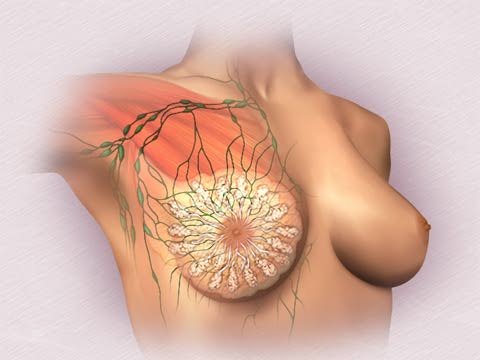

女性乳房

乳房主要由腺体、导管、脂肪组织和纤维组织等构成。其内部结构有如一棵倒着生长的小树。 乳房腺体由15~20个腺叶组成,每一腺叶分成若干个腺小叶,每一腺小叶又由10~100 个腺泡组成。这些腺泡紧密地排列在小乳管 周围,腺泡的开口与小乳管相连。多个小乳管汇集成小叶间乳管,多个小叶间乳管再进一步汇集成一根整个腺叶的乳腺导管,又名输乳管。 输乳管共15~20根,以乳头为中心呈放射状排列,汇集于乳晕,开口于乳头,称为输乳孔。

输乳管在乳头处较为狭窄,继之膨大为壶腹,称为输乳管窦,有储存乳汁的作用。乳腺导管开口处为复层鳞状上皮细胞,狭窄处为 移形上皮,壶腹以下各级导管为双层柱状上皮或单层柱状上皮,终末导管近腺泡处为立方上皮,腺泡内衬立方上皮。 |